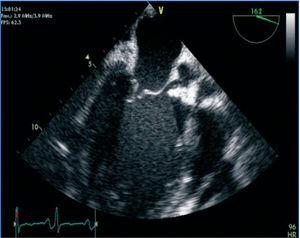

A cardiac ultrasound was performed, showing massive aortic regurgitation (AR) with a preserved left ventricular ejection fraction (LVEF) (69%). Three vegetations were found in the aortic valve, and the largest one measured 20mm. A pericardial haemorrhage was also observed without signs of heart block or thrombi (Figures 1 and 2).

Figure 1. Massive aortic regurgitation.